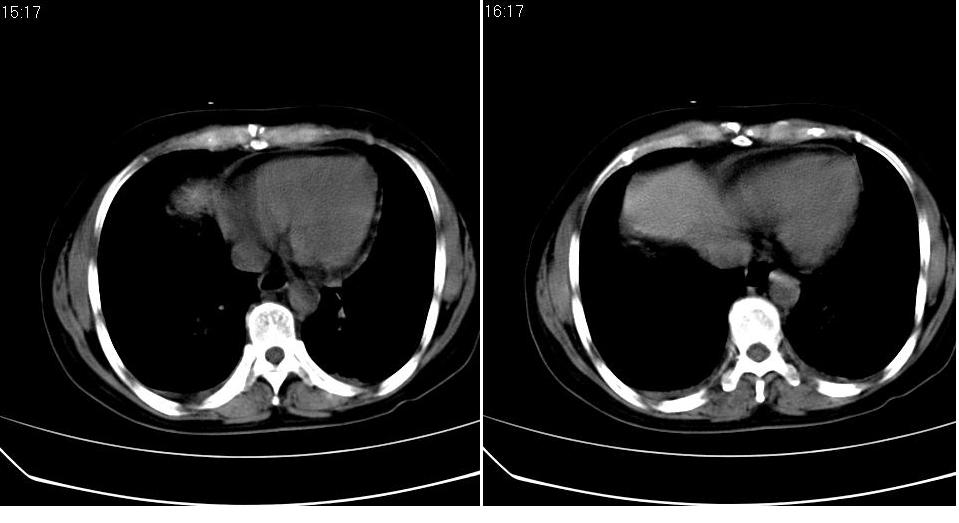

标题: CT16839:胸部CT平扫

女 50岁,在其他医院确诊肺癌.

都已发生广泛转移了,意义不大。

考虑 肺癌伴肺及纵隔转移,心包膜增厚